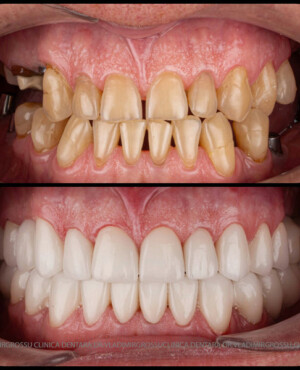

Protezarea pe implanturi dentare este soluția modernă, estetică și funcțională pentru înlocuirea dinților lipsă. Această procedură combină precizia chirurgicală cu tehnologia avansată de laborator pentru a reda pacienților zâmbetul natural, vorbirea clară și capacitatea de a mânca fără restricții.

La Clinica Dentară Dr. Grossu din Chișinău, oferim protezări pe implanturi dentare personalizate, realizate de o echipă multidisciplinară, cu ajutorul celor mai noi tehnologii digitale și materiale biocompatibile.

- Estetică superioară – imită perfect dinții naturali

- Funcționalitate completă – mestecare și vorbire fără restricții

- Durabilitate îndelungată – cu îngrijire corectă, peste 15–20 de ani